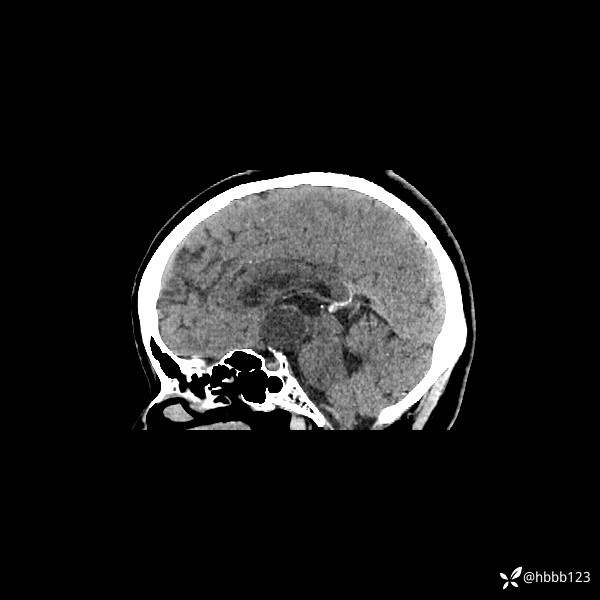

矢状位重建: